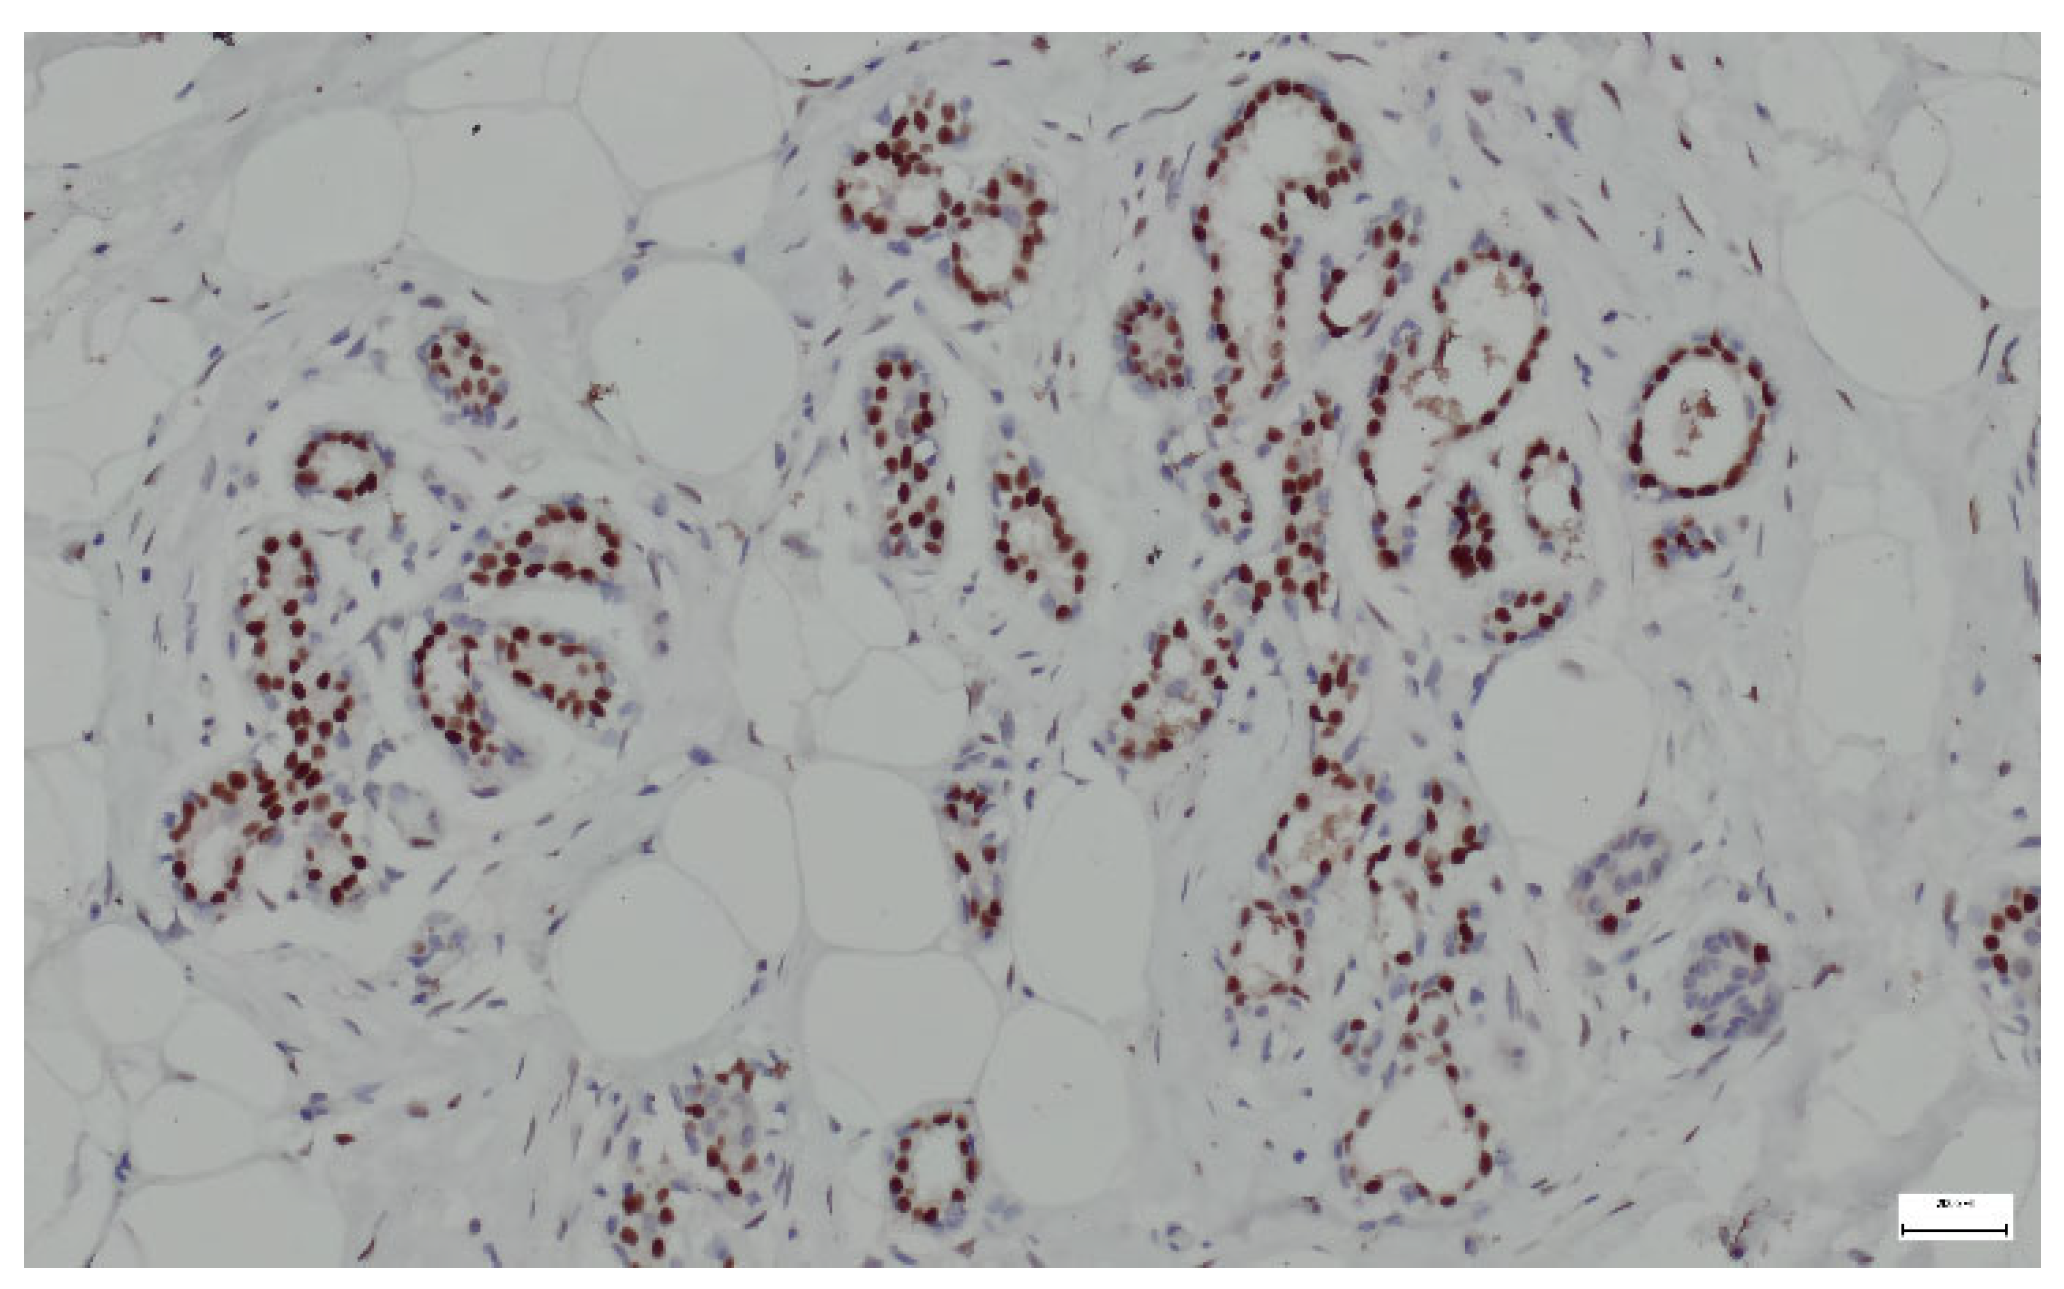

Breast hamartomas often express estrogen receptors (ER), that can be detected in the epithelial cells lining the ducts and lobules within the hamartoma. ER expression was found in all tissue samples (Figure 13).

Figure 13.

ER lining the ducts and lobules in breast hamartoma (anti-ER, ×10).

In addition to histological evaluation, breast hamartoma can be confirmed by IHC, where glandular components that contain normal breast ducts and lobules are highlighted by ER, SMA, and p63. Immunostaining aids in the differentiation of breast hamartomas from malignant lesions and contributes to a detailed characterization of these benign entities. ER expression in breast hamartomas can indicate hormone responsiveness, similar to other benign and malignant breast lesions. ER can also be expressed in the stromal component of the hamartoma, though this is less common. Smooth muscle actin (SMA) staining in breast hamartomas can help identify the presence and distribution of myoepithelial cells around glandular structures. SMA can also stain myofibroblasts in the fibrous stroma of breast hamartomas. The staining can highlight pericytes and smooth muscle cells in the walls of blood vessels within the hamartoma [40]. p63 is a member of the p53 family of transcription factors and is involved in the development and maintenance of epithelial tissues. It is commonly used as a marker for myoepithelial cells in the breast and other tissues. The detection of a continuous layer of p63-positive myoepithelial cells around ducts and lobules supports the diagnosis of a benign lesion [40].